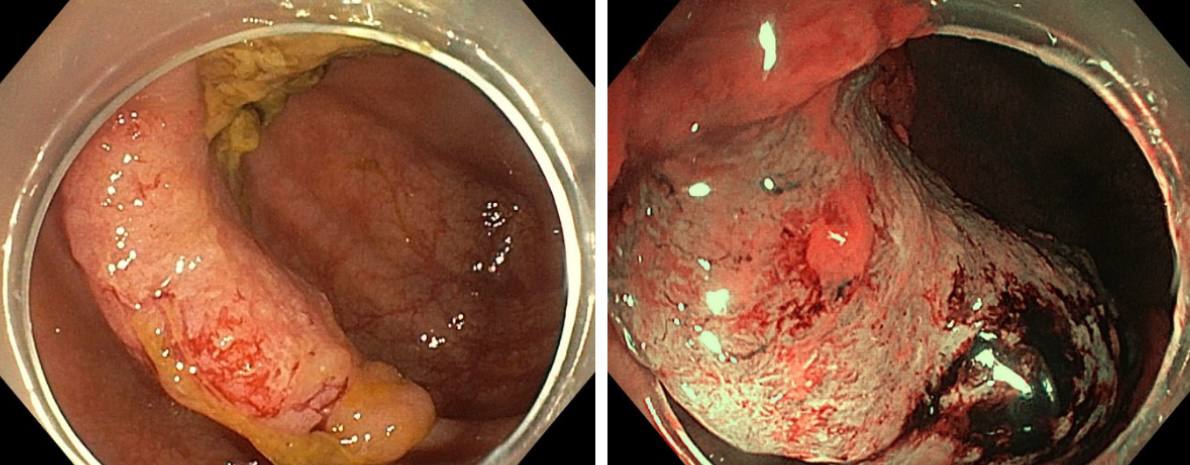

В Клинику факультетской хирургии им. Н.Н. Бурденко Сеченовского Университета поступила пациентка с диагнозом рак пищевода. Диагноз был поставлен женщине по месту жительства. При углубленном обследовании в клинике Сеченовского университета врачи обнаружили у женщины второе онкологическое заболевание — опухоль в восходящем отделе ободочной кишки.

Хирурги провели торако-лапароскопическую субтотальную резекцию пищевода типа МакКеона с лимфаденэктомией и одновременную правостороннюю гемиколэктомию с удалением поражённого участка ободочной кишки. Новый пищевод врачи сформировали из желудка пациентки.